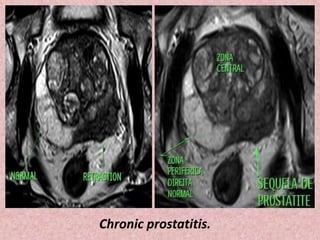

Note extensive low signal intensity (asterisks) throughout the

peripheral zone, indicative of chronic prostatitis

Chronic prostatitis.